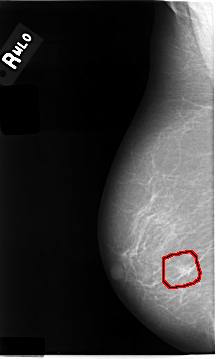

C_0014_1.RIGHT_MLO

FILE: C_0014_1.RIGHT_MLO.OVERLAY

TOTAL_ABNORMALITIES 1

ABNORMALITY 1

LESION_TYPE MASS SHAPE IRREGULAR MARGINS MICROLOBULATED

ASSESSMENT 5

SUBTLETY 4

PATHOLOGY MALIGNANT

TOTAL_OUTLINES 1

BOUNDARY